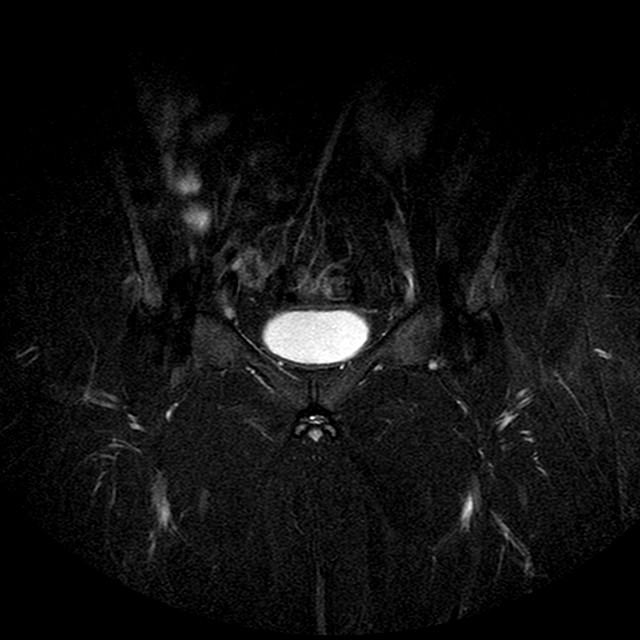

Esami: RMN BACINO

STIR

Evidenti e simmetriche alterazioni osteofitosiche in regione coxo femorale con riduzione delle rime articolari. Degenerazione completa del cercine glenoideo. Non attuali segni di versamento articolare. Non segni di edema osseo che escludono attuale algodistrofia od osteonecrosi. Lieve e simmetrica riduzione del trofismo della muscolatura glutea.